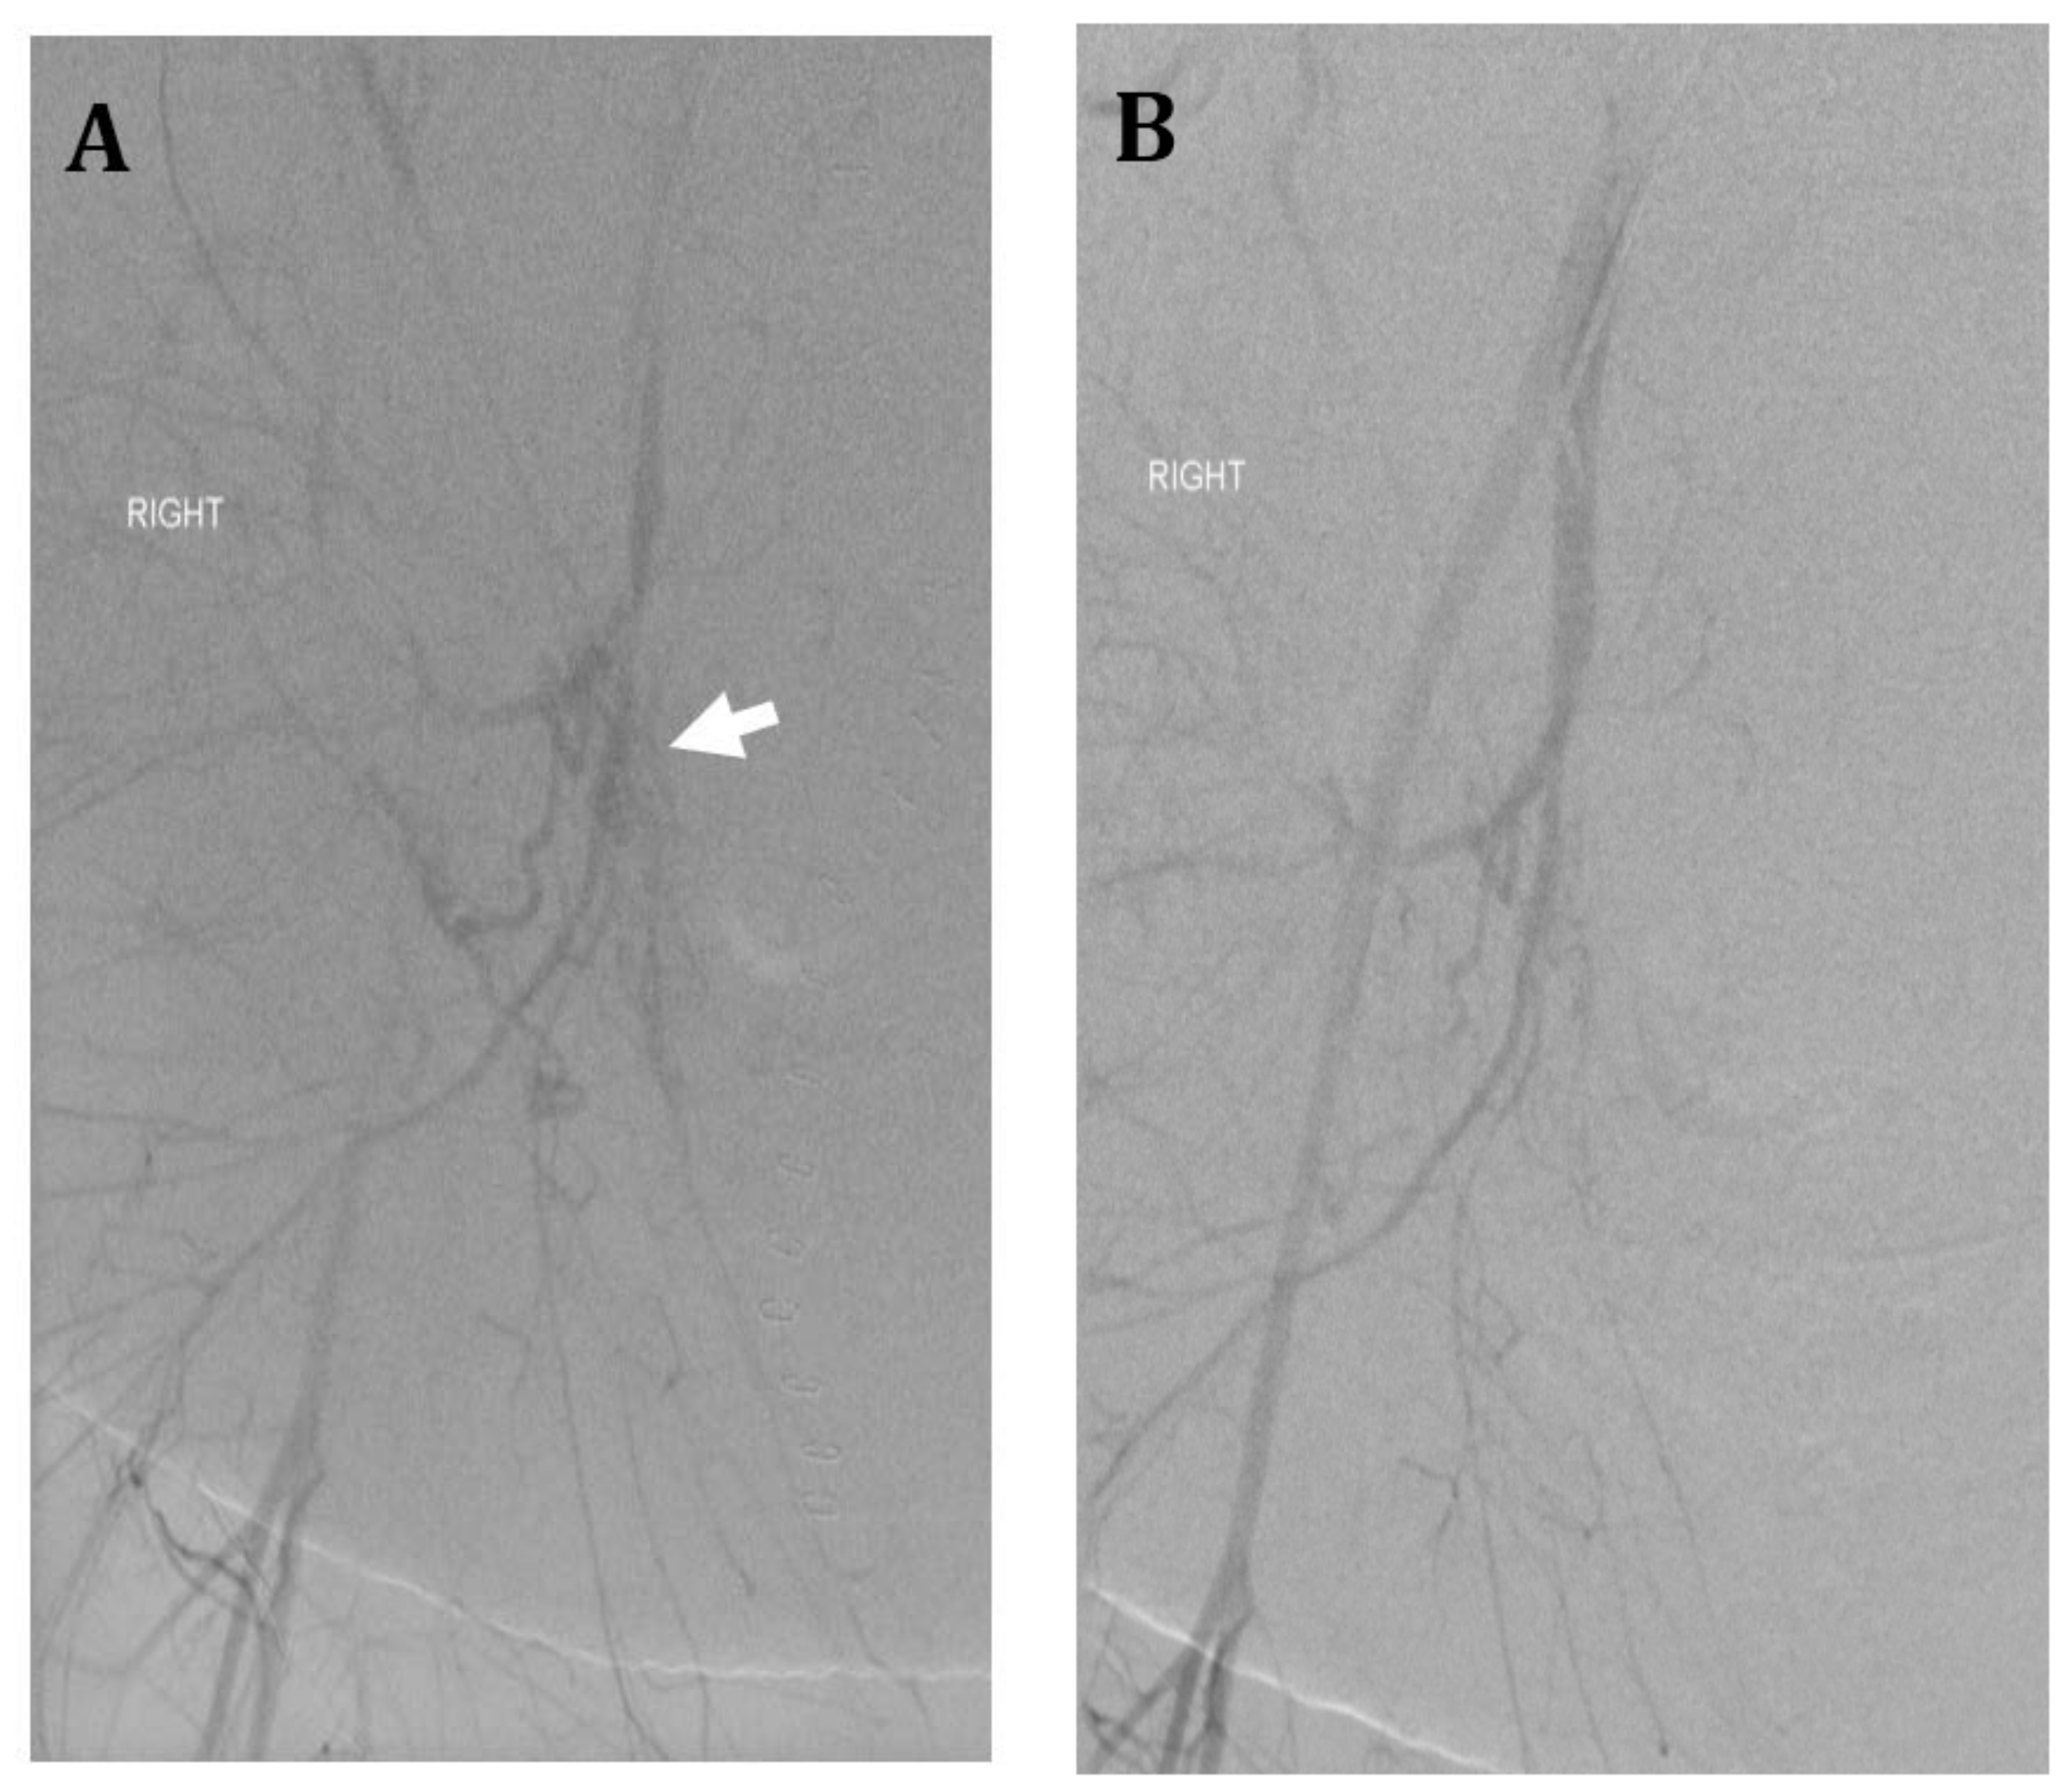

Figure 4.

Thirty-six-year-old female with morbid obesity, severe preeclampsia, and placenta accreta status post cesarean section at 34 weeks. Uterine preservation was performed with incomplete removal of placenta. Patient’s postoperative course was complicated by postoperative bleeding and hypotension requiring massive transfusion and vasopressors. (A) Right internal iliac artery angiogram shows multiple irregular vessels (arrow). Gelfoam embolization of the anterior division was performed until near hemostasis. (B) Post embolization right internal iliac artery angiogram shows no extravasation. Anterior division of left internal iliac artery was also embolized using gelfoam. Despite embolization, patient required hysterectomy for hemorrhagic shock and abdominal compartment syndrome; intraoperative estimated blood loss was approximately 10–15 L. Patient ultimately had a good recovery.